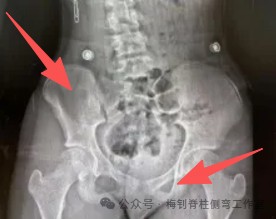

在支具治疗中,家长缺乏必要的知识,很容易听信网络上所谓“专业家长”的评判,对治疗结果产生怀疑,这时可以积极和支具师沟通,分析原因。如下面这个支具的矫正片:

看了这张片子,所谓的“专家”往往是和正常的骨骼对比去简单得到结论:左侧髂骨小,右侧闭孔小,骨盆有明显旋转。但支具师会分析,造成这个结果的原因:从体表看,骨盆没有旋转,但腰椎有旋转;而片子上显示,腰椎没有旋转,而骨盆有旋转。X线片和体表结果相悖,所以,要怀疑是拍片时候的站姿问题,如果拍片时左脚在前就会导致这种结果。分析侧位片,同样需要认真思考,如下图: